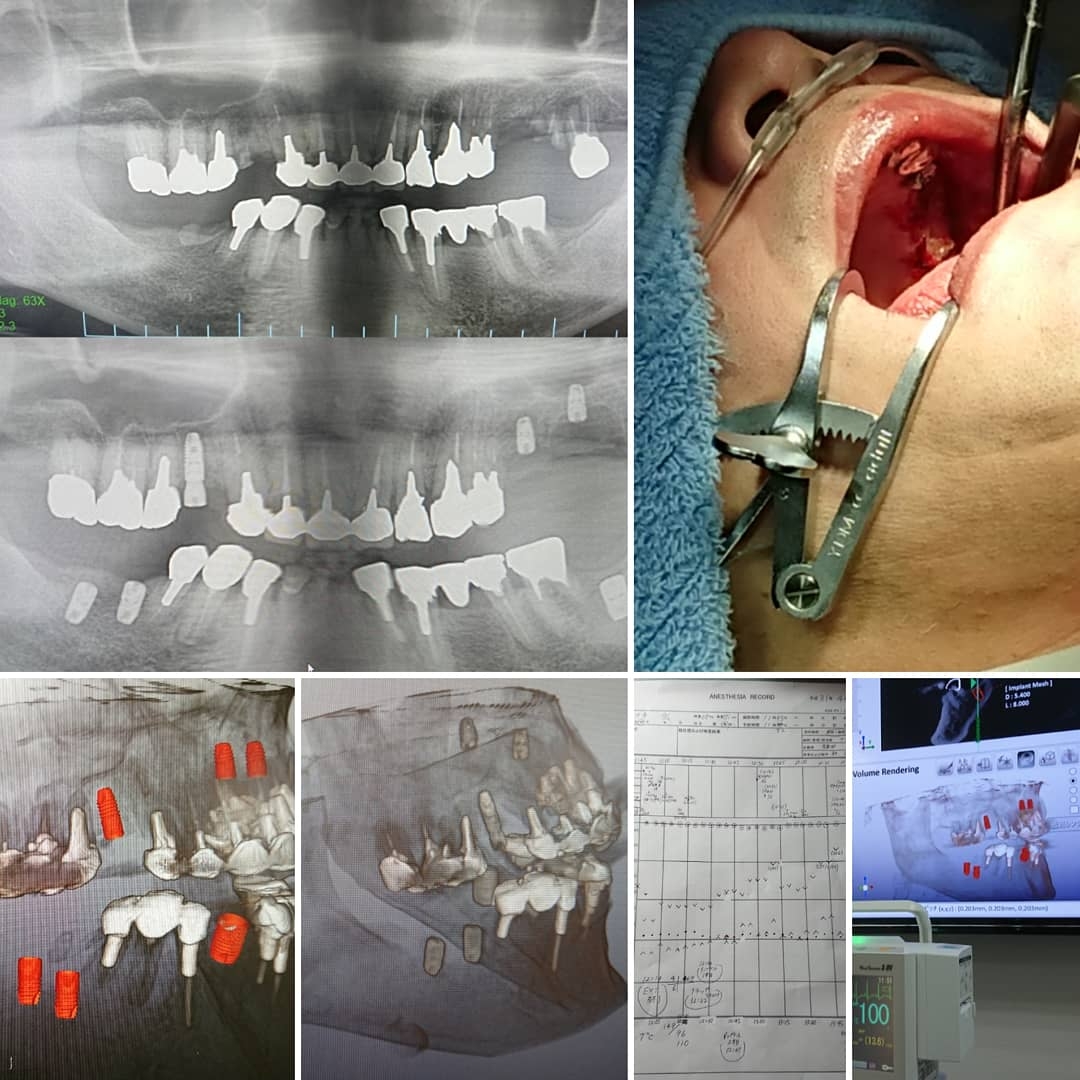

✳️抜歯即日インプラント6本埋入評価‼️(約3時間)

✳️左上術前その↓術後(2D)

✳️鎮静下にて記録‼️

✳️予後良好‼️

✳️本日も感染予防のため点滴(DIV‼️)

✳️左下オレンジ色はシミュレーション。右が埋入結果(3D)

✳️当院歯科口腔外科医師症例